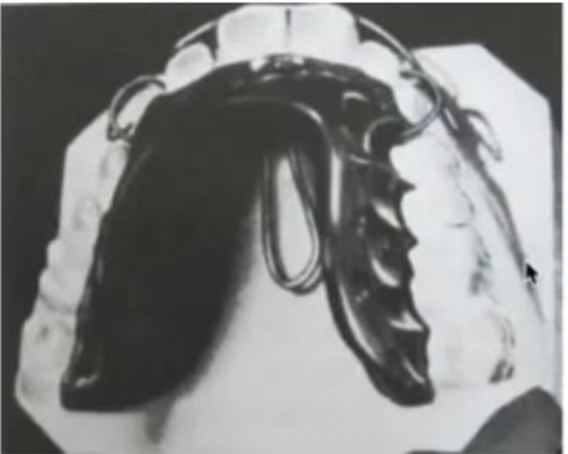

Activator

- Andresen-Haupl activator (II d1)

- Coffin spring: 上顎擴弓+舌頂

- labial loop: 撐開 intercanine

- Labial bow: 限制前牙不移動

- Modified activator (II d1)

- lingual shields: 引導下顎、舌頭

- Mandible ++

- 下顎前旋,讓後牙長高,VD++